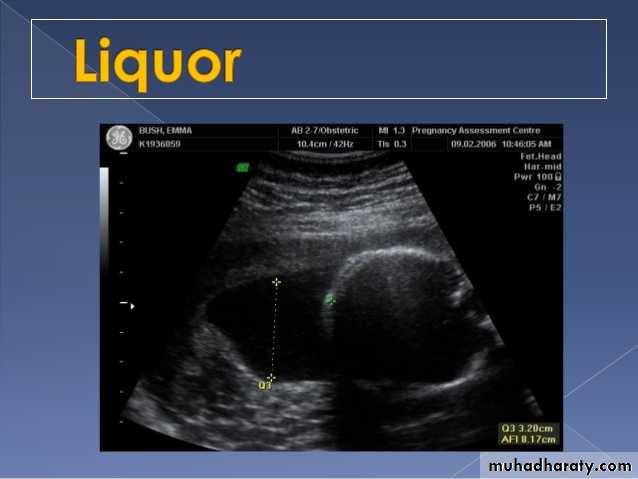

Poly hydraminos refers to a situation where the amniotic fluid volume is more than expected for gestational age.It is generally defined as:

amniotic fluid index (AFI) > 25 cmlargest fluid pocket depth (maximal vertical pocket (MVP)) greater than 8 cm

overall amniotic fluid volume larger than 1500-2000 cc3